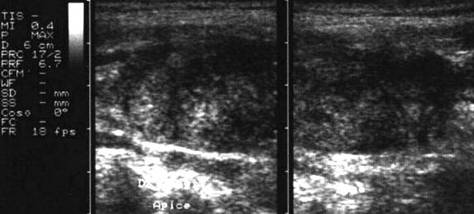

Femeie 32 ani. Nodul unic la apexul lobului drept, contur net, hipoecogen, nu influienteaza parenchimul din jur, neomogen cu arii hiperecogene si hipoecogene, de 12x17x25mm, (2,6 cc).

Citoaspiratia: leziuni foliculare.

Examen histologic postoperator: adenom microfolicular cu aspect trabecular.

ecocolordoppler si powerdoppler- acelasi nodul

Vascularizatie interna, mai evidenta in powerdoppler.